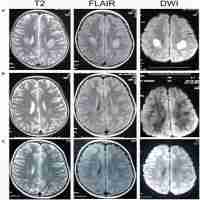

| Description | In this report, we describe a three-generation family (the Gelao nationality, a minority ethnic group from Guizhou Province in the southwest China) with one affected member with Charcot-Marie-Tooth neuropathy X type 1 (CMTX1) in each generation. The three affected members carrying the R164W mutation in the Cx32 gene had different clinical symptoms. The proband, a 13-year-old boy presented recurrent episodes of transient central nervous system symptoms and concomitant transient diffuse white matter lesions on magnetic resonance imaging. His grandfather had the peripheral neurological presentations with later onset in the fourth decade, characterized by slowly progressive weakness of the distal muscles, atrophy, and foot deformities. But no sensory loss was observed. The proband's 38-year-old mother denied any neurological symptoms. The examination was normal except for pes cavus and diminished deep tendon reflexes in her lower limbs bilaterally. Genetic sequencing revealed the proband and his grandfather had a hemizygous mutation (p.164R > W) of CJB1 gene, and his mother had R164W heterozygous mutation. Our three cases denied symptoms of sensory disturbances, the sensory examination including touch, pin prick, and temperature sensation showed no obvious abnormalities. Thus, further investigation is needed to improve our understanding of the Cx32 protein function in the nervous system. Supplementary data (Table S1 and Fig. S1) are available at: www.thieme-connect.com/products/ejournals/html/10.1055/s-0035-1564619). |